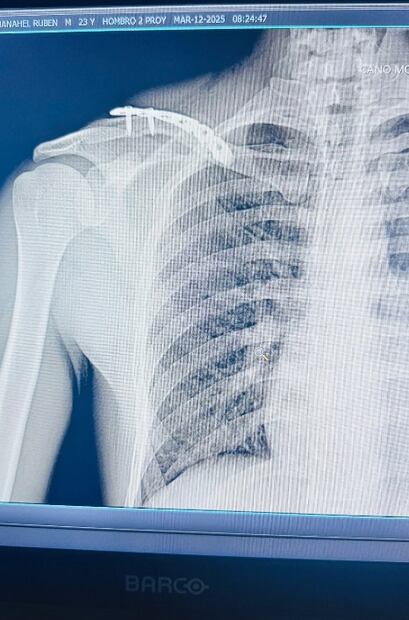

A través de su cuenta de Instagram, la voz detrás de "Madonna" compartió fotos de las acrobacias que realizó en el aire. En la descripción, añadió: “Clavícula salió del chat”, junto con emoticones de caritas riendo. También publicó las radiografías de la fractura en su clavícula.

Según explicó su doctor, al artista le fueron colocados cinco clavos de titanio en el hueso afectado. "Para que no se oxide el muchachón", bromeó el famoso.